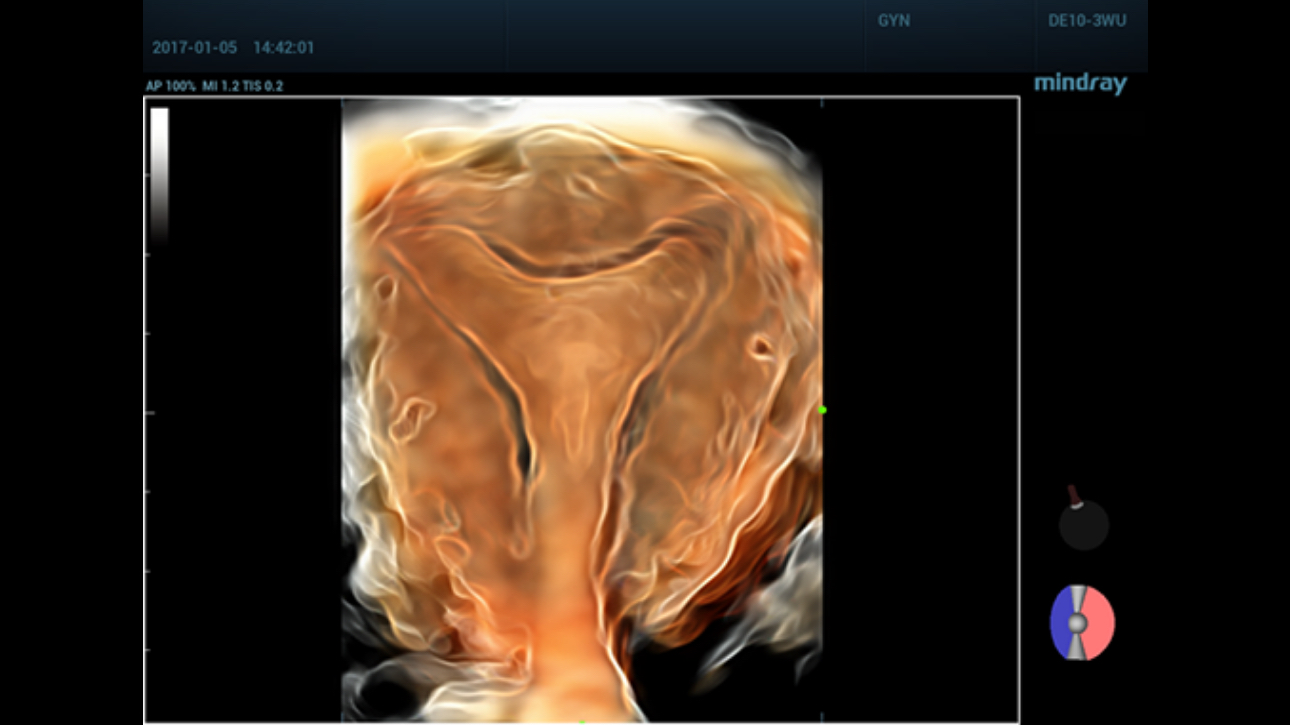

Comprehensive upgrading on iLive to significantly improve the detailed resolution as well as anatomical realism. Hyaline is a new rendering method that dynamically applies transparency to rendered structures for a more comprehensive view of anatomy, therefore better displaying internal anatomy from a solid surface.